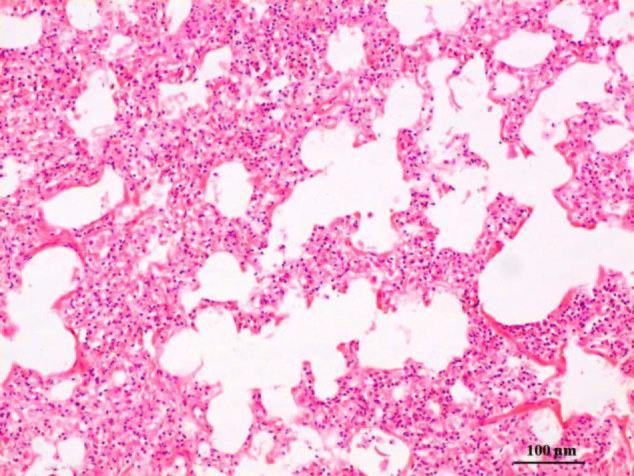

Results: BRDC cases exhibited 0.98% BCoV occurrence, confirmed by partial N gene amplification (172 bp) via RT-PCR and immunohistochemistry (IHC). Grossly, 4 BCoV positive cases showed variable degrees of consolidation of cranioventral lobes and non-collapsed caudodorsal lobes, associated with congestion and emphysema. Microscopically, the inflated sites of the lung tissue sections showed hallmark changes of interstitial pneumonia characterized by moderate infiltration with lymphocytes and increased numbers of fibroblasts in the interalveolar septa and the stroma of bronchioles and bronchi. In concomitant Pasteurella multocida infected cases, cranioventral lobes exhibited suppurative bronchopneumonia with neutrophilic exudate. The above lesions were well colocalized with BCoV antigen in the epithelial cells and in the debris of the lumen of the alveoli and the bronchi/bronchioles. The sequence comparison of the 172 bp amplicon with the published BCoV N gene showed close relatedness.